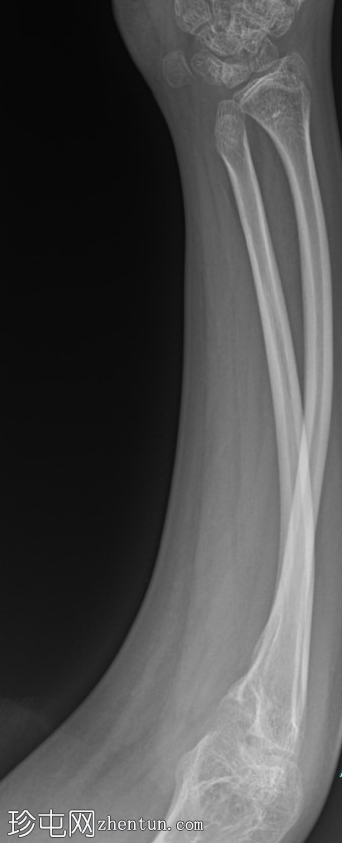

肱骨X光片 - 右侧

X光片

右肱骨中段骨干粉碎性骨折,伴有外侧移位和内侧成角。

周围软组织明显肿胀和畸形。